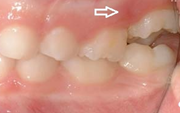

) Röntgenülesvõte. Ülemise esimese jäävmolaari lõikumine on takistatud 2. piimamolaari tõttu

Esimese jäävmolaari ektoopiline lõikumine